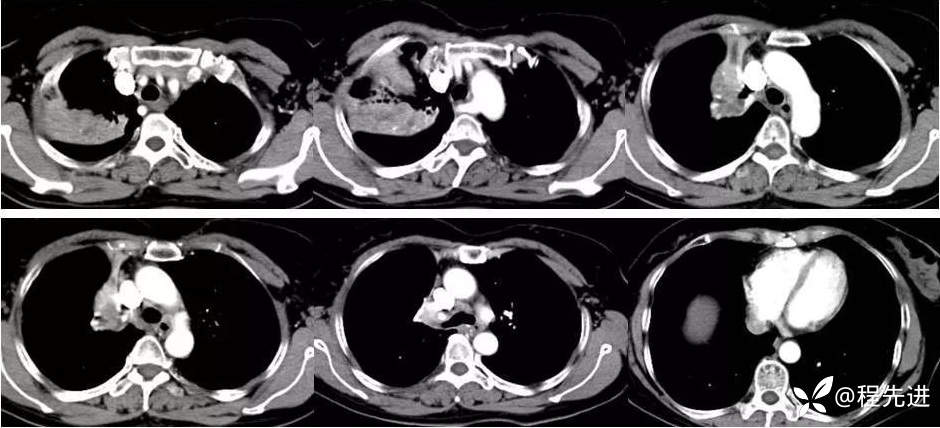

本院胸部CT增强: